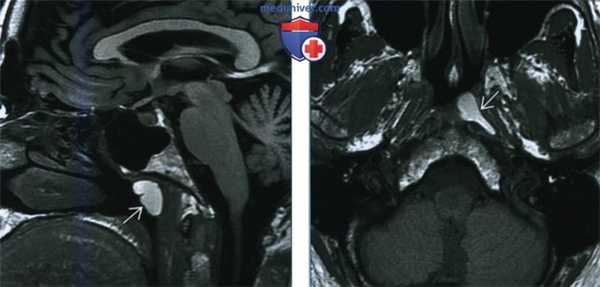

(Слева) При МРТ Т1ВИ в сагиттальной проекции визуализируется типичная ретенционная киста с гладкими контурами, расположенная на задней стенке носоглотки. Образование напоминает кисту Торнвальда, но на аксиальных срезах видно, что она имеет парамедианное расположение.

(Справа) МРТ Т1ВИ в аксиальной проекции, этот же пациент. Ретенционная киста латерального глоточного кармана с характерной грушевидной формой. Обратите внимание, что содержимое кисты отличает гиперинтенсивный сигнал. Это говорит либо о геморрагическом, либо высокобелковом содержимом кисты.